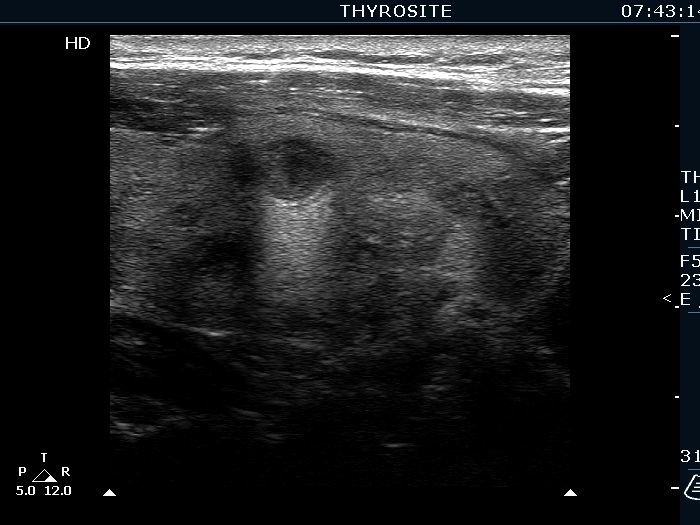

Ultrasonography. The right lobe was echonormal and presented several hypoechoic nodules. A large, inhomogeneous, partly deeply hypoechoic, partly minimally hypoechoic or echonormal mass occupied the left lobe. The borders of the tumor were irregular. There were multiple lymph nodules upper and lateral to the left thyroid lobe. The nodes had a heterogeneous pattern and lacked hilum. The vascularity was scanty both in the thyroid nodules and the lymph nodes.